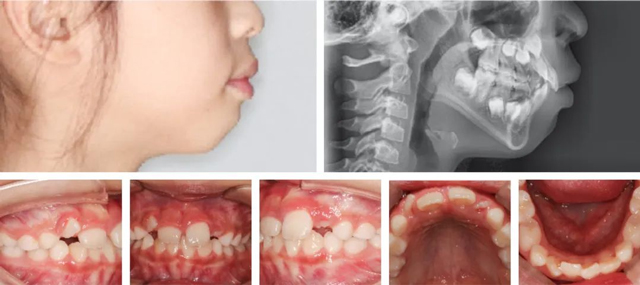

经过详细检查,并结合数字化口扫、CBCT和头颅侧位片,医生发现朵朵侧貌上唇前突,闭唇时颏肌和唇肌紧张,闭嘴困难,出现了“腺样体面容”:上牙前突、唇外翻、唇形肥厚、下巴收紧等。

矫正前